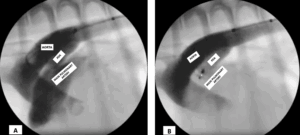

For pets with PDA, the most common option today is to deploy a device via the aorta into the PDA to permanently occlude it. Initially, small coils were used, and they are occasionally still used. Currently, a specific device called the Amplatz Canine Ductal Occluder (ACDO) is used to occlude the pet’s PDA (Figure 2).

The ACDO device resembles a two-sided umbrella that is opened inside the PDA, with a portion of the device on each side of the PDA opening. The size of this device is typically selected by the veterinary cardiologist based on the size of your pet’s PDA, ensuring it fits snugly within the PDA and causes almost immediate clotting, thereby occluding the shunting of blood (Figure 3).